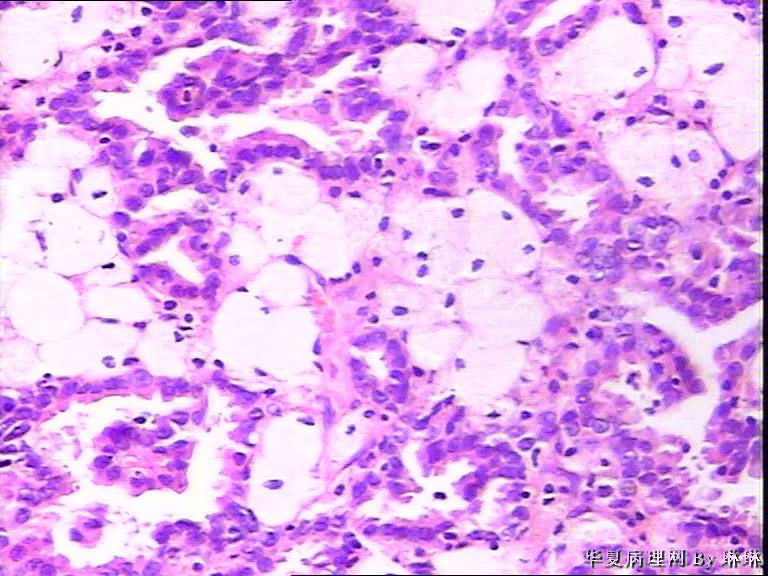

患者男性,50岁,右肾外伤可见一淡黄色圆形肿物,包膜完整,部分突出于肾表面,直径约3.5cm,切面淡黄色,质软。请各位看看,多多发表见解。

• 右肾肿瘤,请教!图2

图2

仔细看看有没有乳头状结构,要先考虑乳头状肾细胞癌,1 型。

考虑乳头状肾细胞癌

感觉还像透明细胞肾癌。

乳头状肾细胞癌